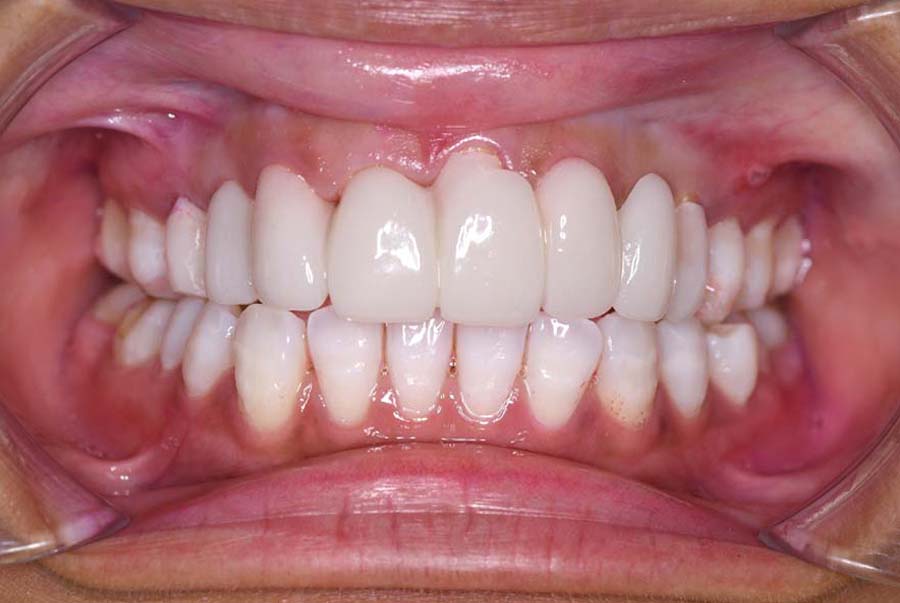

スプリント使用後、

補綴治療をした症例

⑤2024年5月 上顎前歯部8本へ仮歯(TEK)

を装着